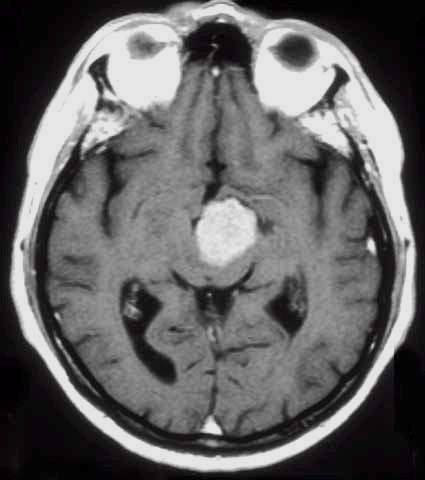

Glioma

ad alto grado di malignità (Glioblastoma) |

Lesioni caratterizzate da un accrescimento veloce con infiltrazione del tessuto cerebrale attiguo e diffusione a distanza di cellule maligne.

Scopo della chirurgia è ridurre macroscopicamente la massa tumorale per facilitare ulteriori trattamenti (principalmente radio - chemioterapia mentre altri protocolli terapeutici sono ancora in fase di studio).

In queste lesioni la loro conformazione anatomica, praticamente sempre di tipo II (Daumas-Duport) non ha un ruolo così dirimente nell'indicazione chirurgica poiché il comportamento biologico è sicuramente il fattore più importante.

RM:

glioma con segni di trasformazione maligna